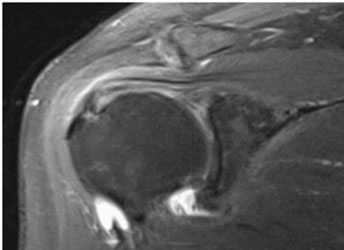

Импинджмент-синдром.а. МРТ плечевого сустава, б. рентгенография плечевого сустава.

Для верификации диагноза используют также тест с введением лидокаина (с стероидами) в суставную сумку. Это вызывает временное уменьшение интенсивности боли.